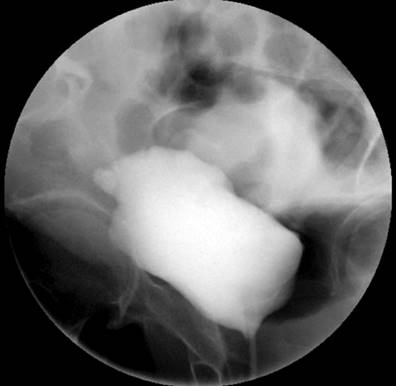

Due to the recurrence of the symptoms, chronicity, absence of etiology after a detailed study, and taking into account the patient’s surgical history, less frequent etiologies were considered a possibility of uroperitoneum. Creatinine was measured in the peritoneal fluid, the result of which was 7.44 mg/dL, and the gradient between fluid and serum was 5.74, which further increased the suspicion. Due to the uncertainty in the face of acute kidney injury and suspicion of urinary fistula, the nephrology service requested a voiding cystography with dynamic films, finding a bladder dome defect with active contrast extravasation into the peritoneal cavity, which confirmed the presence of uroperitoneum and explained the elevation of nitrogenous gases that simulated acute renal injury (Figure 1). To better characterize the genitourinary tract lesion and surgical planning, a urotomography was performed (Figure 2) with evidence of a defect in the bladder dome of 7.8 mm towards the right side in its anterior portion, with evidence of extraluminization of the contrast medium as a sign of rupture. After this characterization, he was scheduled for laparotomy with cystorrhaphy, performed at another institution.

Voiding cystography is the gold standard for diagnosing bladder rupture, with a sensitivity and specificity of 95% and 100%, respectively33. However, with the availability of new techniques, CT cystography has a performance comparable to voiding cystography, especially if injuries to other organs must be ruled out, which is common in traumatic bladder ruptures in multiple trauma patients33,34.